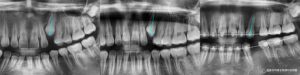

안녕하세요 양원역 교정치과 김정은 원장입니다 ~ 자녀의 영구치가 모두 올라와야 할 시기인데 유독 송곳니만 보이지 않는다면 단순히 늦게 나오는 것이 아닐 수 있습니다. 이런 경우 매복치일 가능성을 염두에 두고 정밀한…